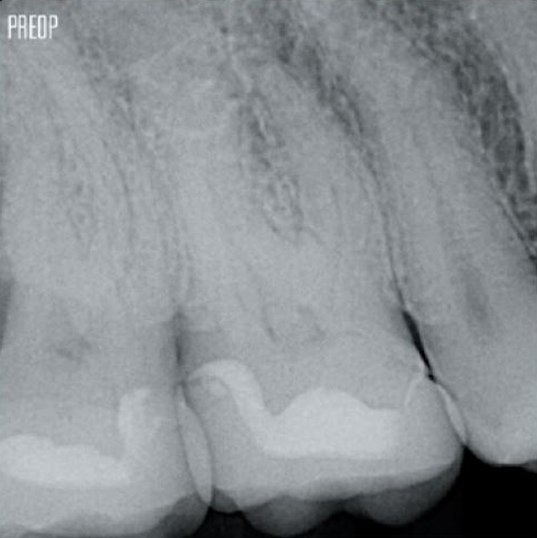

Photos courtesy of Dr. Ahmed Salman

Retaining dentin serves as the critical base for a quality restoration following root canal treatment. The more dentin preserved during an endodontic treatment, the more options there will be to perform a successful, durable restoration.1

Successful root canal treatment starts with adequate access to the pulp chamber. The ideal procedure provides access to root canal orifices with minimal loss of dentin.

A Conservative Endodontic Cavity (CEC) is the recommended with the TruNatomy® system.

The union of the file geometry, regressive tapers and the slim, highly-flexible wire enables efficient root canal treatment while removing only dentin where clinically needed.1

More dentin preserved. Appropiate shaping, irrigation, and obturation ensured.